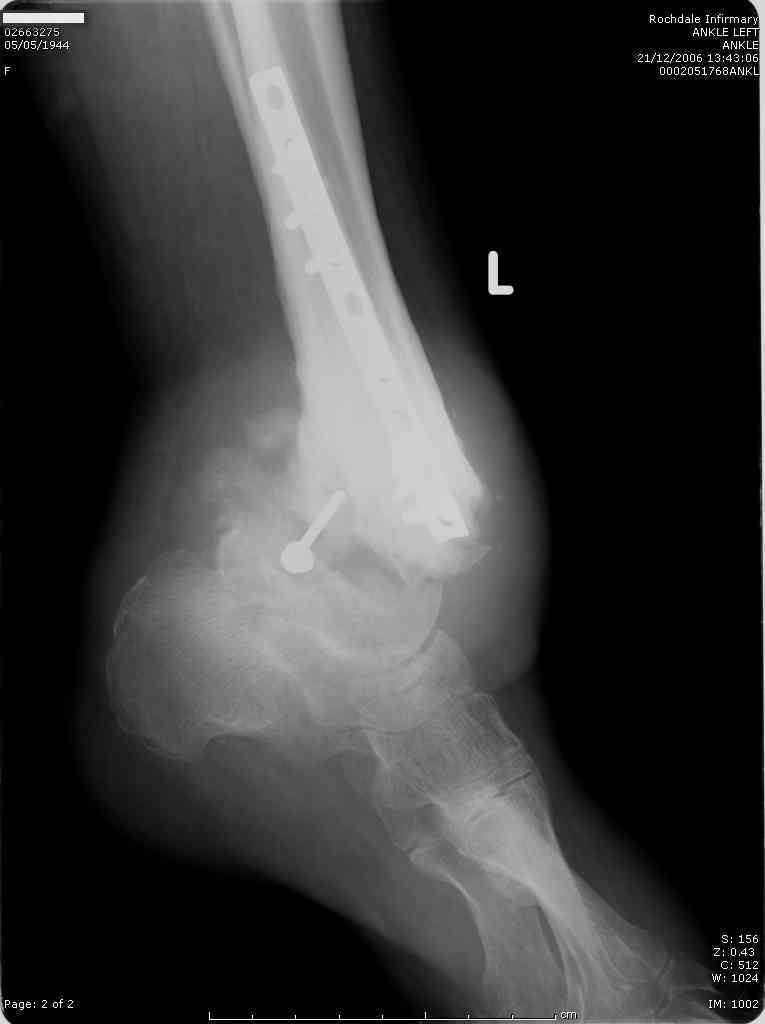

62 year old femaie, registered blind, IDDM with peripheral neuropathy, Diabetic nephropathy, and blindness - also most likely due to dabetic retinopathy, referred to me with deformity of the ankle and an ulcer on the lateral malleolus, No pain.

H/O ORIF both ankles 2 years ago for Bilateral ankle fractures. The otherside is doing well.

It is obviously a Charcot's ankle but what are the options? B K Amputation or a TTC fusion after removal of metalwork and healing of ulcer? Patient wants to walk and a bit reluctant for an amputation which is my preferred option. Any suggestions?